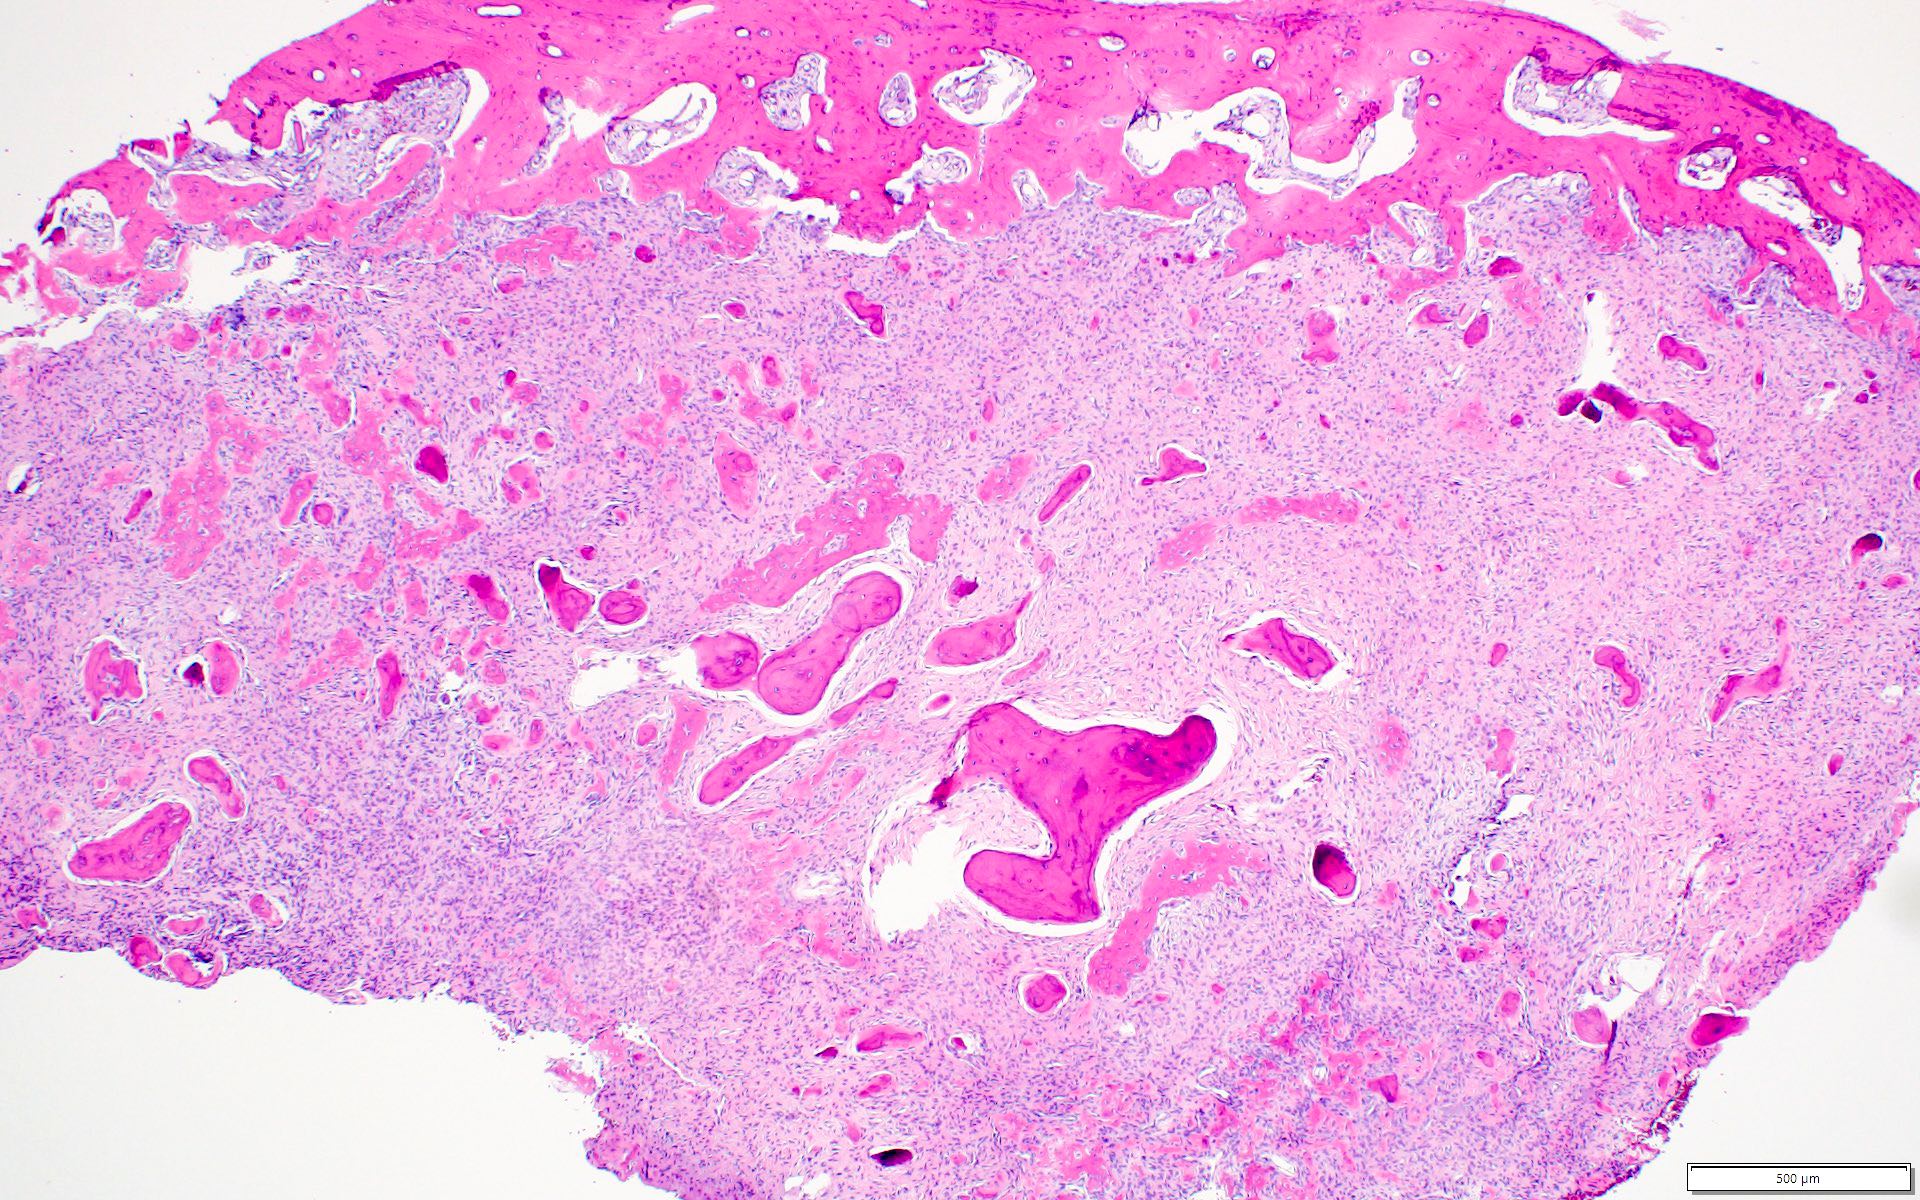

Microscopic (histologic) description

- Well defined lesion; may have thin fibrous capsule

- Well demarcated margin from surrounding normal bone

- Lesion consists of variable proportion of fibrous and mineralized tissue, more heavily mineralized centrally; it shows variation in the amount and type of mineralization, even within a single lesion

- Osteoblastic rimming of bone trabeculae is frequent (J Stomatol Oral Maxillofac Surg 2022;123:364)

- Stroma is fibroblastic with areas of hypercellularity and nuclear hyperchromasia

- No significant atypia and mitoses are infrequent (Head Neck Pathol 2020;14:70)

- Woven to lamellar bone, osteoid and dense acellular or paucicellular basophilic rounded cementum-like calcifications may all be present (Head Neck Pathol 2020;14:70)

- Bony trabeculae may form thick anastomosing strands or fuse into large sheets centrally

- Hemorrhagic cystic degeneration, resembling aneurysmal bone cyst formation, is more often found in juvenile active ossifying fibromas but has been reported in rare COFs (J Stomatol Oral Maxillofac Surg 2022;123:364, Head Neck Pathol 2022;16:248)

Microscopic (histologic) images

Contributed by Saira Javeed, M.B.B.S., M.Phil., Kelly Magliocca, D.D.S., M.P.H. and Molly Housley Smith, D.M.D.